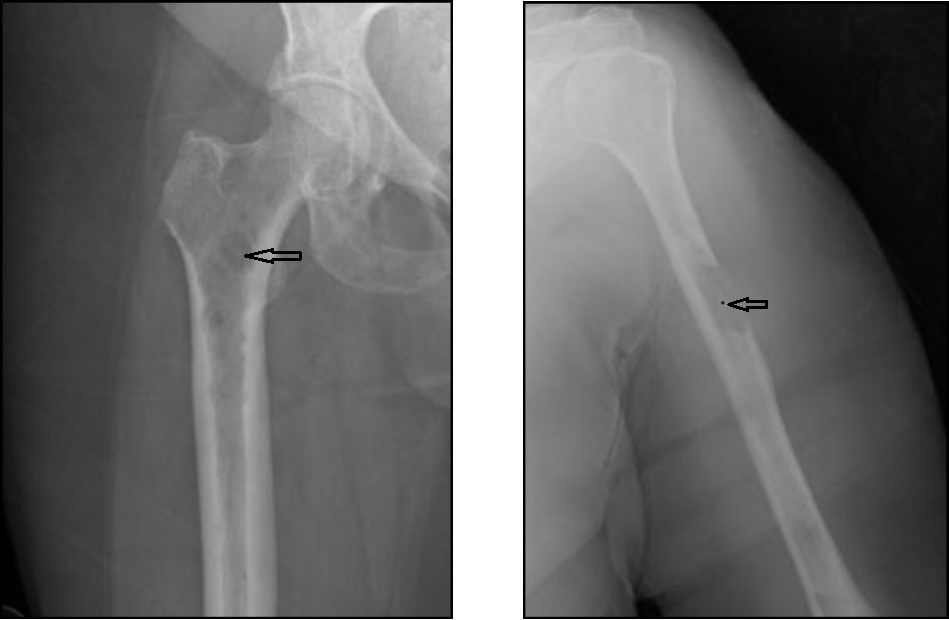

Fifty-seven-year-old female with a history of hypertension presented with progressively worsening shoulder and back pain. Physical exam was significant for diffuse bone tenderness. Bone skeletal survey showed multiple punched out lesions (Figure 1A, Figure 1B), diffuse demineralization and compression fracture in T12 and L1. Laboratory findings were significant for anemia (hemoglobin 6.2 g/dL) with peripheral blood smear revealing rouleaux formation, hyponatremia 126 mmol/L, elevated creatinine 3.23 mg/dL with blood urea nitrogen 45 mg/dL, albumin of 3.1 g/dL, hypercalcemia 15.5 mg/dL (corrected calcium 16.2) and marked hyperphosphatemia 20.5 mg/dL. Patient had high serum viscosity 3.1 centipoises, elevated total protein levels 11.9 g/dL, elevated IgA 4598 mg/dL, low IgG 580 mg/dL and low IgM 24 mg/dL. Inorganic phosphorous measurements on deproteinized serum samples revealed normal phosphorous levels. Parathyroid hormone and 25-OH vitamin D levels were normal. An increased AG of 24 was observed after correcting for albumin. An electrocardiogram revealed osborn waves in the setting of severe hypercalcemia. Serum, urine protein electrophoresis and bone marrow biopsy were performed, and she was diagnosed as IgA kappa type mutiple myeloma. MRI spine revealed rostrocaudal cord edema spanning T10-T12 secondary to significant cord compression requiring emergent intravenous steroids (Figure 2). Patient was managed with intravenous fluids and pamidronate for hypercalcemia. Due to refractory nature of hypercalcemia patient required urgent hemodialysis.

Figure 1.A Multiple focal and diffuse small lucencies throughout the right upper femurs (most prominent marked with an arrow). Figure 1. B Multiple lucencies throughout left humerus with a destructive large lesion in the upper third region.